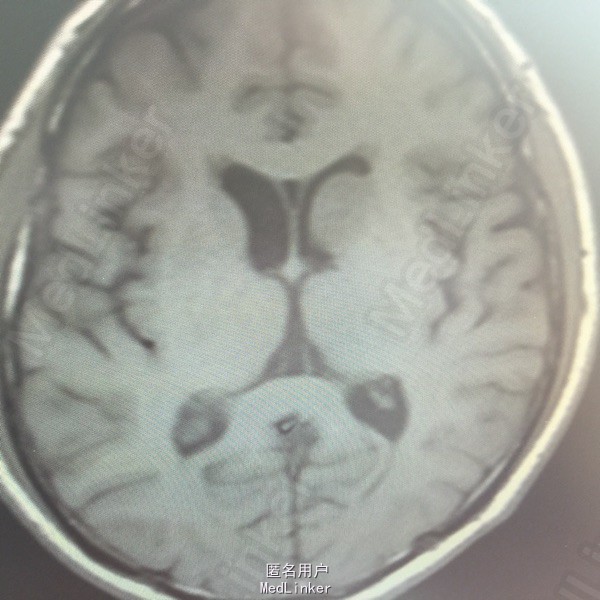

男,54岁,以头痛半个月入院。 现病史:半个月前无诱因头痛,呈胀痛,无呕吐,无意识障碍,病来咳嗽、咳痰,体重减轻约5斤,无发热。 既往史:无特殊。

查体:BP:150/100mmHg,神清语明,两瞳孔等大正圆,直径约3.0mm,光敏,四肢肌力5级,肌张力正常,腱反射艹,左侧共济运动阳性,病理征阳性,脑膜刺激征(-)。 辅查:见下:

肺癌脑转移。 影像解读(影像如何解读是临床工作中非常重要的一环)。 左侧额叶近皮质长Tl长T2信号,局部颅骨缺损,右侧枕叶不规则病灶,TlWl呈中心呈等信号,周围高信号,T2Wl呈高低混杂信号,伴大片水肿,相邻侧脑室后角、胼胝体受压。增强呈不规则环环强化。 已进行局部放疗治疗。